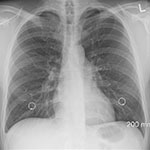

本邦では、StageI/IIA(UICC第8版)以外でPS0~2の限局型小細胞肺がん(LD-SCLC)の治療は、プラチナ製剤を用いた同時化学放射線療法(cCRT)および初回治療で完全寛解が得られた患者への予防的頭蓋照射(PCI)が、標準治療となっている。新たな治療法として、cCRT後のデュルバルマブ地固め療法が有用である可能性が示された。国際共同第III相無作為化比較試験「ADRIATIC試験」の第1回中間解析において、cCRT後のデュルバルマブ地固め療法が全生存期間(OS)と無増悪生存期間(PFS)を有意に改善した。米国臨床腫瘍学会年次総会(2024 ASCO Annual Meeting)で、米国・Sarah Cannon Research InstituteのDavid R. Spigel氏が本研究結果を報告した。

・対象:I~III期(I/II期は外科手術不能の患者)でPS0/1のLD-SCLC患者のうち、cCRT後に病勢進行が認められなかった患者730例(PCIの有無は問わない)